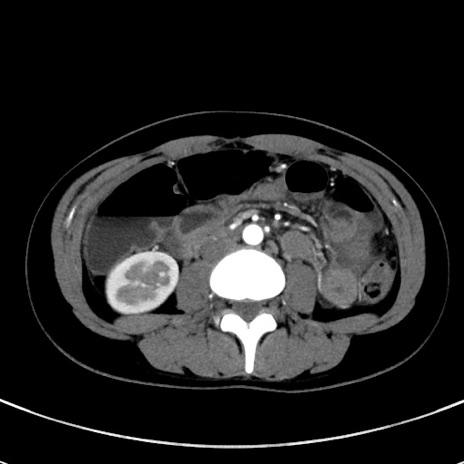

症例17(横断像)

【症例】20歳代女性

【主訴】嘔吐、下腹部痛

【現病歴】昨日夕食後に嘔吐し下腹部痛が出現。本日になっても嘔吐持続し改善しないため来院。

【身体所見】意識清明、BT 37.2℃、BP 108/67mmHg、腹部:平坦、やや硬、下腹部正中から右にかけて圧痛あり、反跳痛軽度あり、tapping pain(+)。

【データ】WBC 13600、CRP 14.94